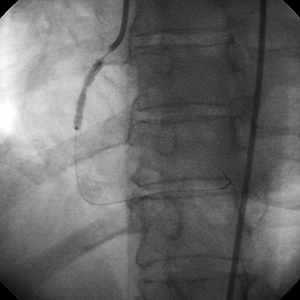

Posdilatación

• Se usaron balones de alta presión de 3,5 mm y 4 mm para postdilatar el stent.

• Los balones de alta presión no tuvieron éxito en la optimización de la expansión del stent.

"Esta RCA altamente estenosada contenía un grado significativo de calcio que no podría apreciarse plenamente en el momento de la angiografía. Cabe destacar que el segmento calcificado no se encontraba en la región de estrechamiento más crítico. Sin embargo, la lesión calcificada no se pudo dilatar después de la aplicación del stent.

Si la dilatación previa del vaso se hubiese realizado antes de la aplicación del stent, la necesidad de usar el sistema Rotablator™ habría sido obvia, y posiblemente se habría evitado la dificultad que se encontró al tratar este vaso."